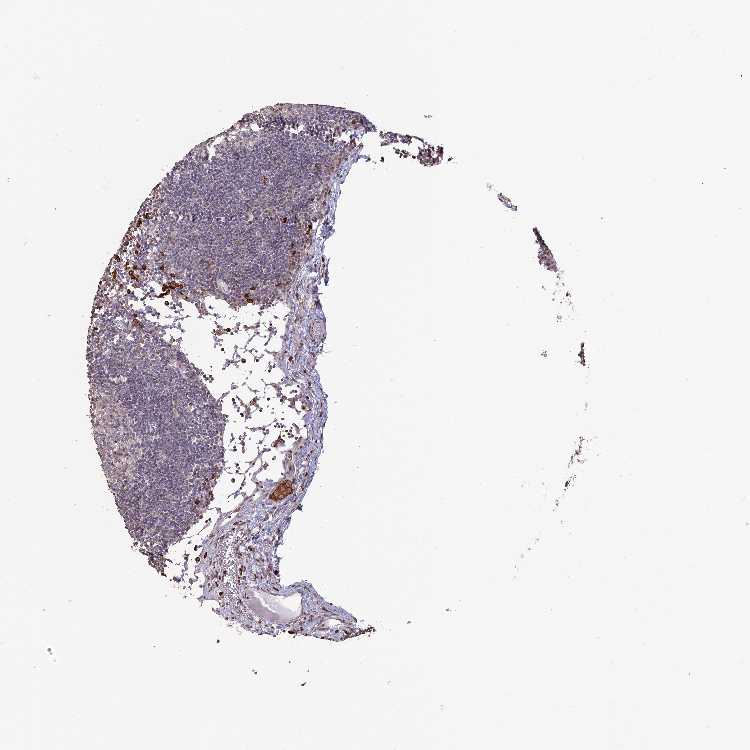

TISSUE PRIMARY DATA LYMPH NODE Show tissue menu

Lymph node

LYMPH NODE - Antibody stainingi

Antibody staining in the annotated cell types in the current human tissue is reported as not detected, low, medium, or high, based on conventional immunohistochemistry profiling in selected tissues. This score is based on the combination of the staining intensity and fraction of stained cells.

Each image is clickable and will lead to virtual microscopy that enables deeper exploration of all samples and also displays staining intensity scores, fraction scores and subcellular localization as well as patient and tissue information for each sample.

Antibody HPA041667Antibody HPA042093

Germinal center cells Not detectedNot detected

Non-germinal center cells MediumLow